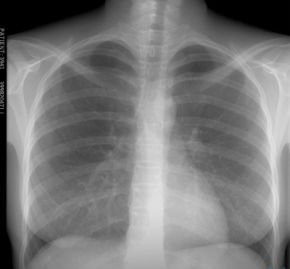

До 2015-го від туберкульозу помруть 10 мільйонів людей, – ВООЗ

За оцінками міжнародної організації, нині від туберкульозу щорічно помирають близько 2 мільйонів людей. Більшість цих смертей припадає на Азію, Африку і Східну Європу.

В Україні виліковуються лише 55-59% хворих на туберкульоз.